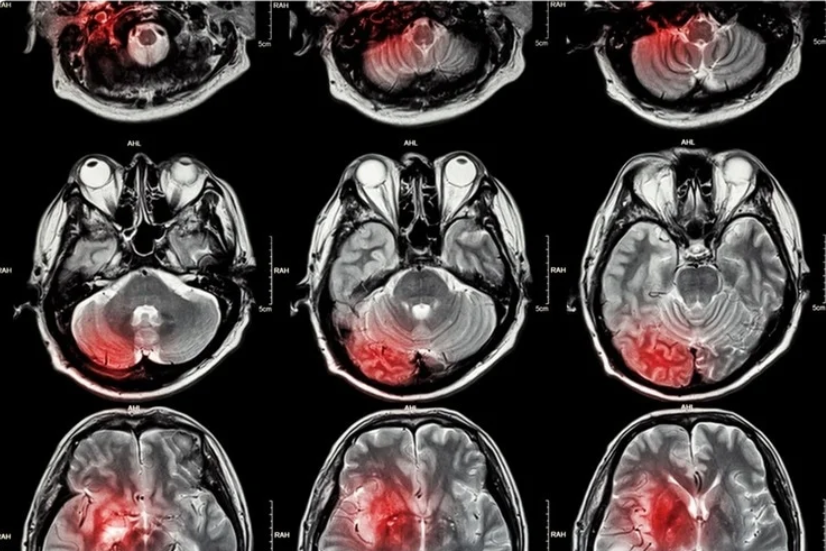

Инсульт и микроинсульт на МРТ

Специалисты выделяют следующие МР-признаки таких патологий:

• снижение скоростных и объемных показателей церебрального кровотока;

• отечность коры больших полушарий и снижение сигнала;

• трудно дифференцировать серое и белое вещество;

• выявление кальцифицированных эмболов;

• обнаружение объемных образований (гематома);

• определение продуктов распада крови;

• гиперинтенсивный сигнал.

Неврологи знакомы с МР-характеристиками разных форм и стадий острого нарушения мозгового кровообращения. Они без труда выполняют диагностику по данным сканирования и подбирают соответствующее лечение. Полученные визуальные данные хорошо дополняют результаты ультразвукового исследования, лабораторных тестов и других процедуры.